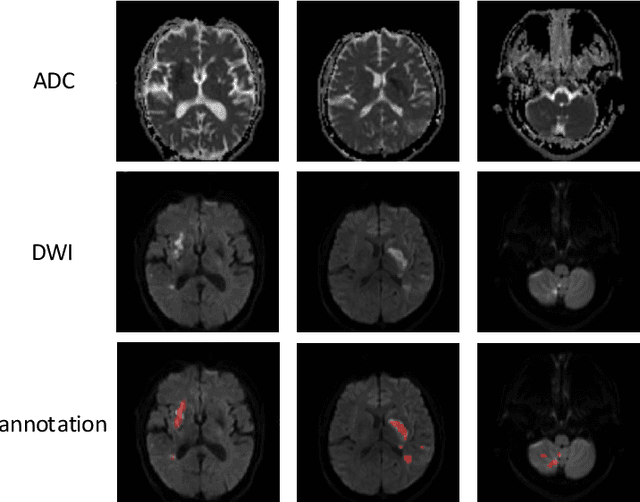

Abstract:Ischemic stroke is a common disease in the elderly population, which can cause long-term disability and even death. However, the time window for treatment of ischemic stroke in its acute stage is very short. To fast localize and quantitively evaluate the acute ischemic stroke (AIS) lesions, many deep-learning-based lesion segmentation methods have been proposed in the literature, where a deep convolutional neural network (CNN) was trained on hundreds of fully labeled subjects with accurate annotations of AIS lesions. Despite that high segmentation accuracy can be achieved, the accurate labels should be annotated by experienced clinicians, and it is therefore very time-consuming to obtain a large number of fully labeled subjects. In this paper, we propose a semi-supervised method to automatically segment AIS lesions in diffusion weighted images and apparent diffusion coefficient maps. By using a large number of weakly labeled subjects and a small number of fully labeled subjects, our proposed method is able to accurately detect and segment the AIS lesions. In particular, our proposed method consists of three parts: 1) a double-path classification net (DPC-Net) trained in a weakly-supervised way is used to detect the suspicious regions of AIS lesions; 2) a pixel-level K-Means clustering algorithm is used to identify the hyperintensive regions on the DWIs; and 3) a region-growing algorithm combines the outputs of the DPC-Net and the K-Means to obtain the final precise lesion segmentation. In our experiment, we use 460 weakly labeled subjects and 15 fully labeled subjects to train and fine-tune the proposed method. By evaluating on a clinical dataset with 150 fully labeled subjects, our proposed method achieves a mean dice coefficient of 0.639, and a lesion-wise F1 score of 0.799.